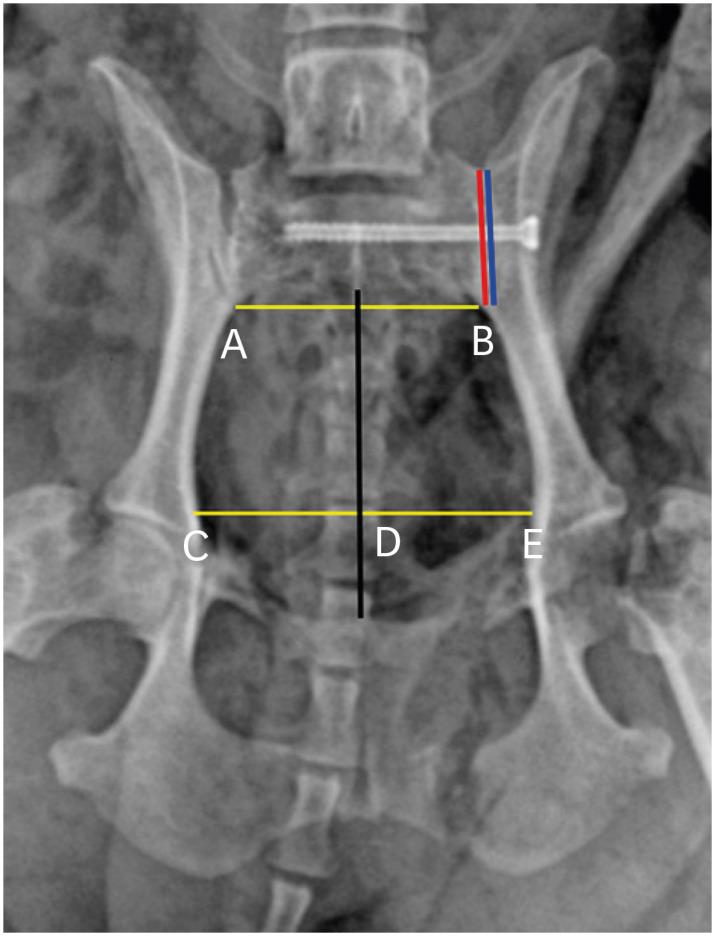

MIS using 2.3-mm cannulated screws was demonstrated in 12 toy breed dog cadavers with sacroiliac luxation artificially induced. Pre and postoperative radiographs were used to evaluate the pelvic canal diameter ratio (PCDR), hemipelvic canal width ratio (HCWR), and reduction rate. Dorsoventral angle (DVA) and craniocaudal angle (CCA) of the inserted screw were obtained postoperative computed tomographic scan.

The statistically significant difference between the mean pre and postoperative PCDR was found (1.10 ± 0.12 and 1.26 ± 0.11, respectively; = 0.002), and the mean HCWR close to 1.0 meaning symmetric pelvis also was obtained (0.97 ± 0.07). The mean DVA and CCA were 2.26° ± 1.33° and 2.60° ± 1.86°, respectively.